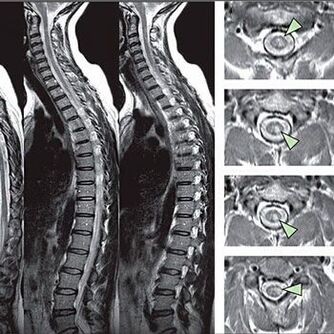

Um Anzeichen von Sensitivitätsstörungen zu identifizieren, werden spezielle Funktionstests durchgeführt. Die informativste Option für die Diagnose aus instrumentellen Methoden ist die Leistung eines X -Strahls. Für eine gründliche Untersuchung der Wirbelsäule werden jedoch häufig MRT und CT durchgeführt. Im Falle eines Verdachts auf Krankheiten des kardiovaskulären Systems wird der Patient empfohlen, sich dem EKG -Verfahren zu unterziehen.